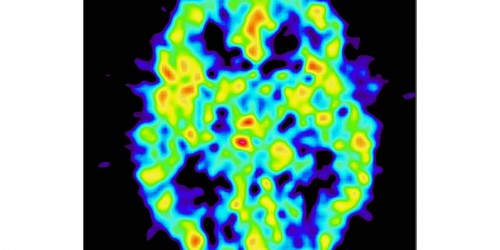

Hello. I have Hydrocephalus on the brain, I've been dealing with this for 13 years now. I have had 5 spinal taps done though out the course of my life! since it very rare in adults, know seems to no exactly what cause this. I just start smelling smoke, and my nose burns all the time!!! This started about a couple of months ago.